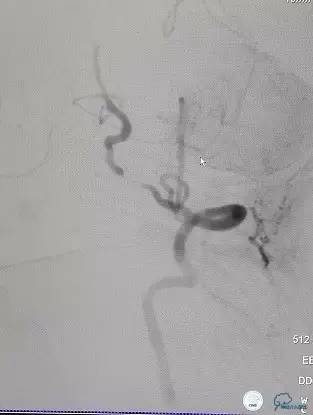

术前DSA(图7-8):右侧椎动脉颅外段纤细,非优势供血,颅内段以远未见显影;左侧椎动脉颅内段PICA动脉以远次全闭塞(狭窄率约为95%以上),基底动脉缓慢浅淡显影,双侧大脑后动脉未见显影。左侧前循环通过后交通动脉向后循环部分区域代偿供血。

图7

图8